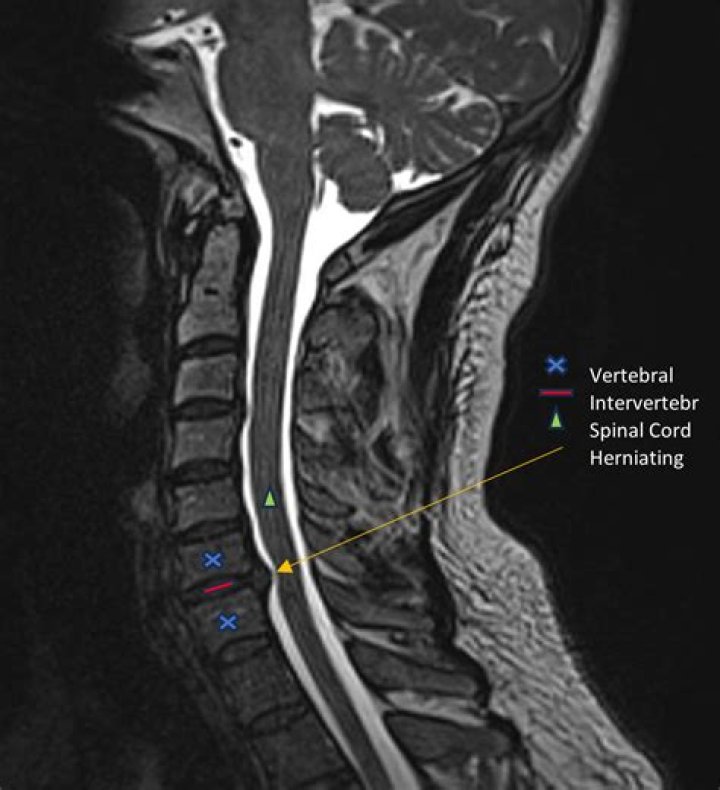

MRI scans which show soft tissues, such as nerves and discs, are generally preferred over CT scans which show bony elements. Advanced imaging can show exactly which nerve or nerves are being pinched and what is causing the nerve to be pinched.

MRIs are able to provide in-depth information on not only the spinal cord but individual nerves as well. There is a good chance that an MRI should be able to detect a pinched nerve.

Clinical Series: How to See a Pinched Nerve (Foraminal Stenosis) on MRI